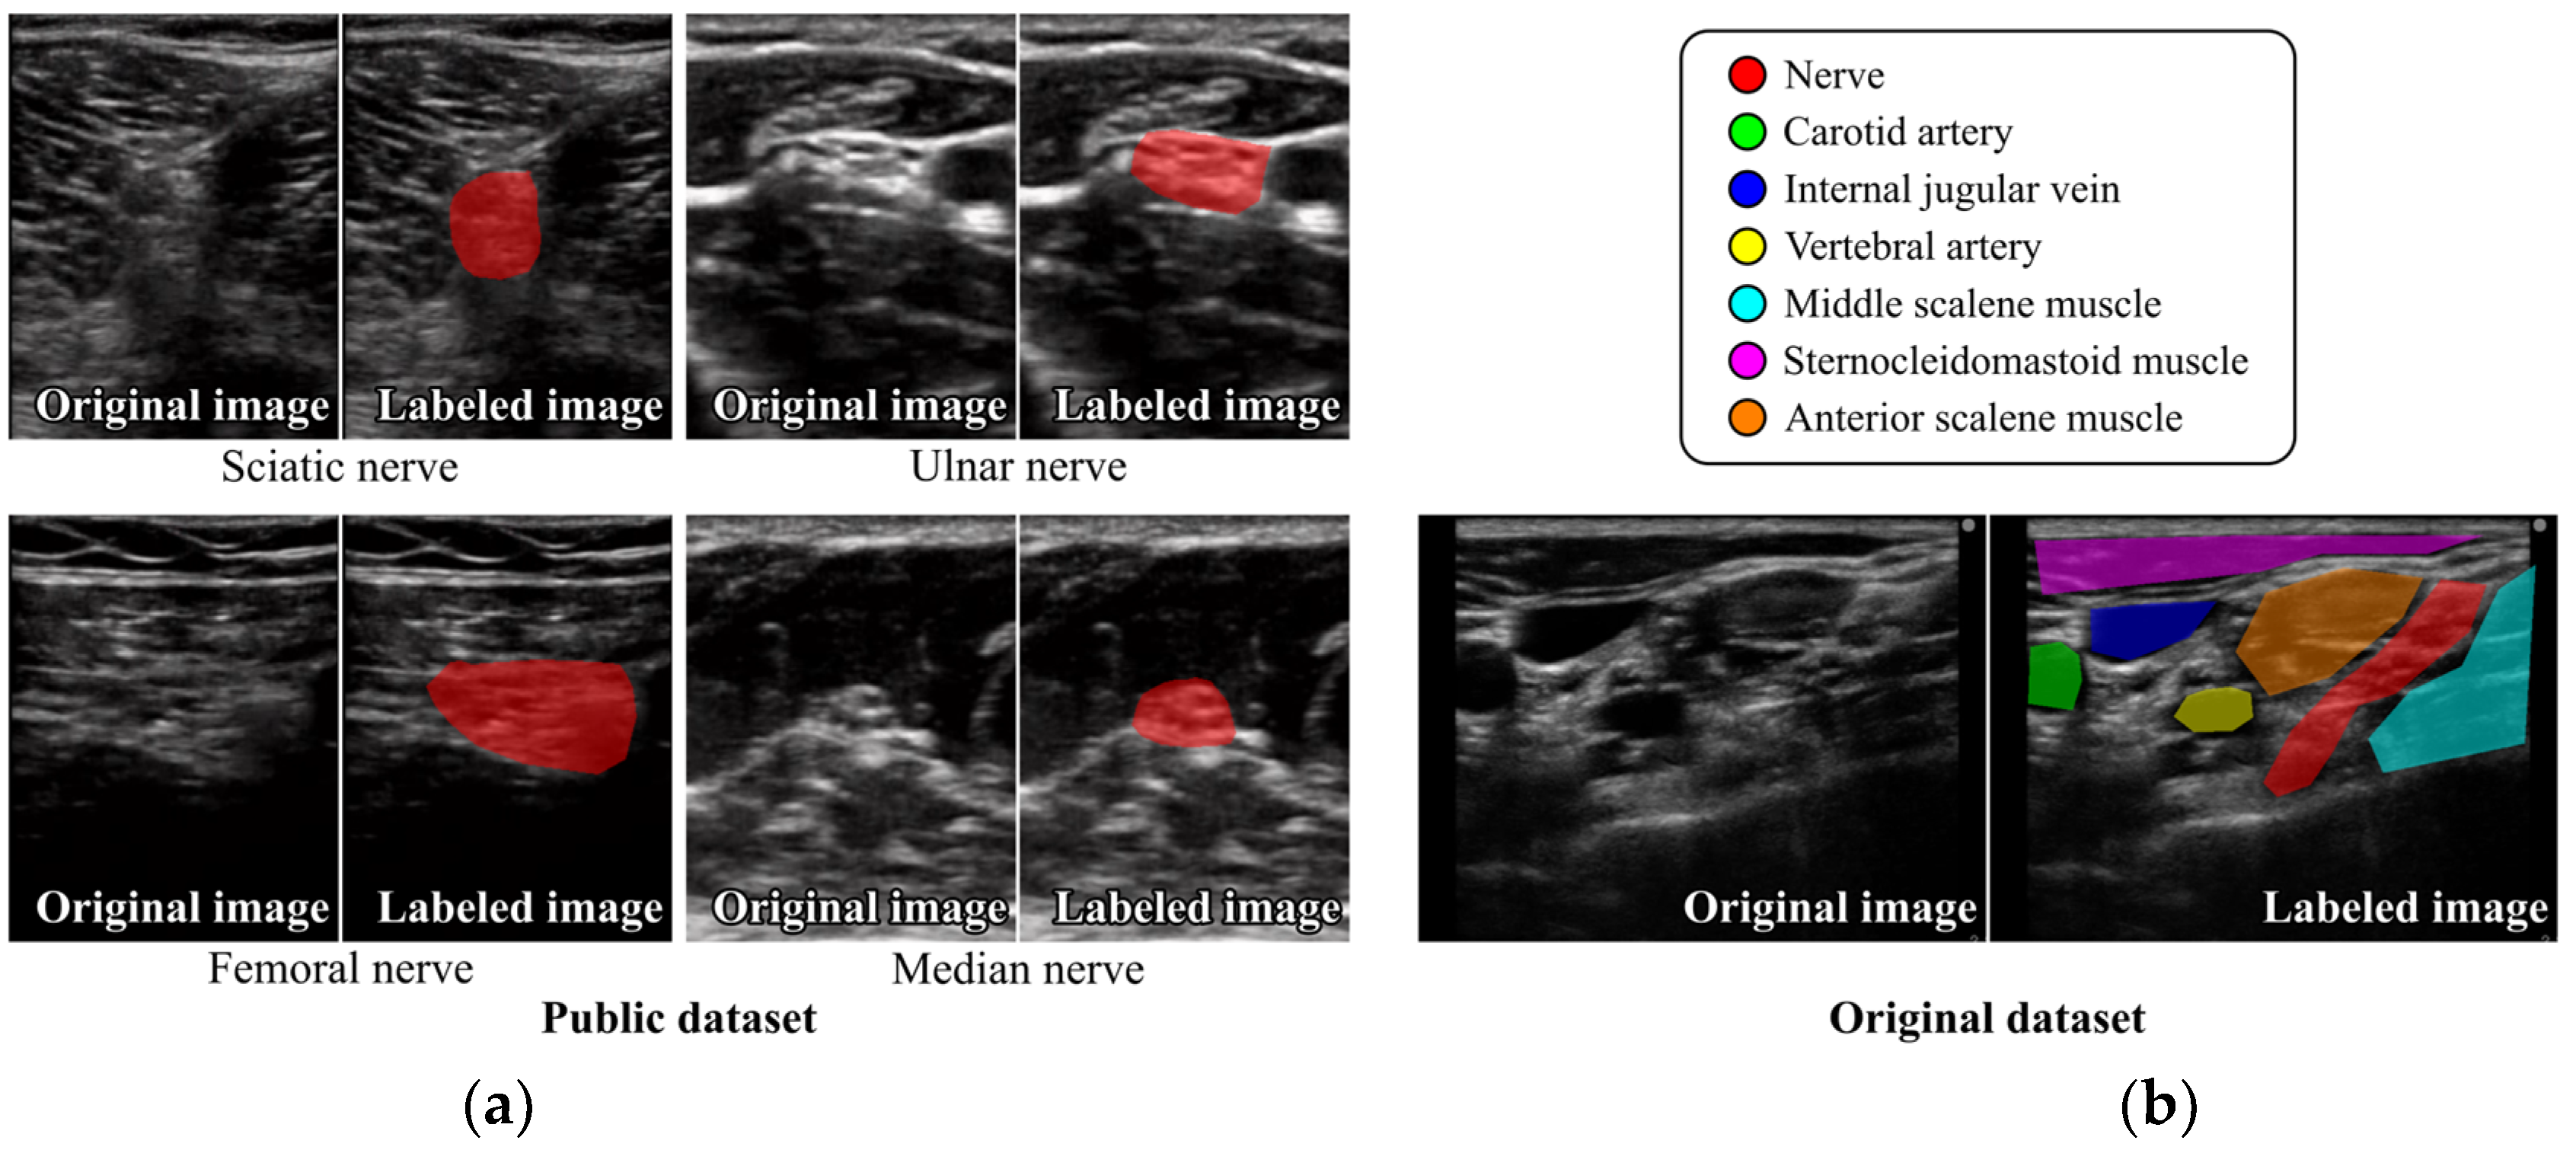

2.1. Dataset